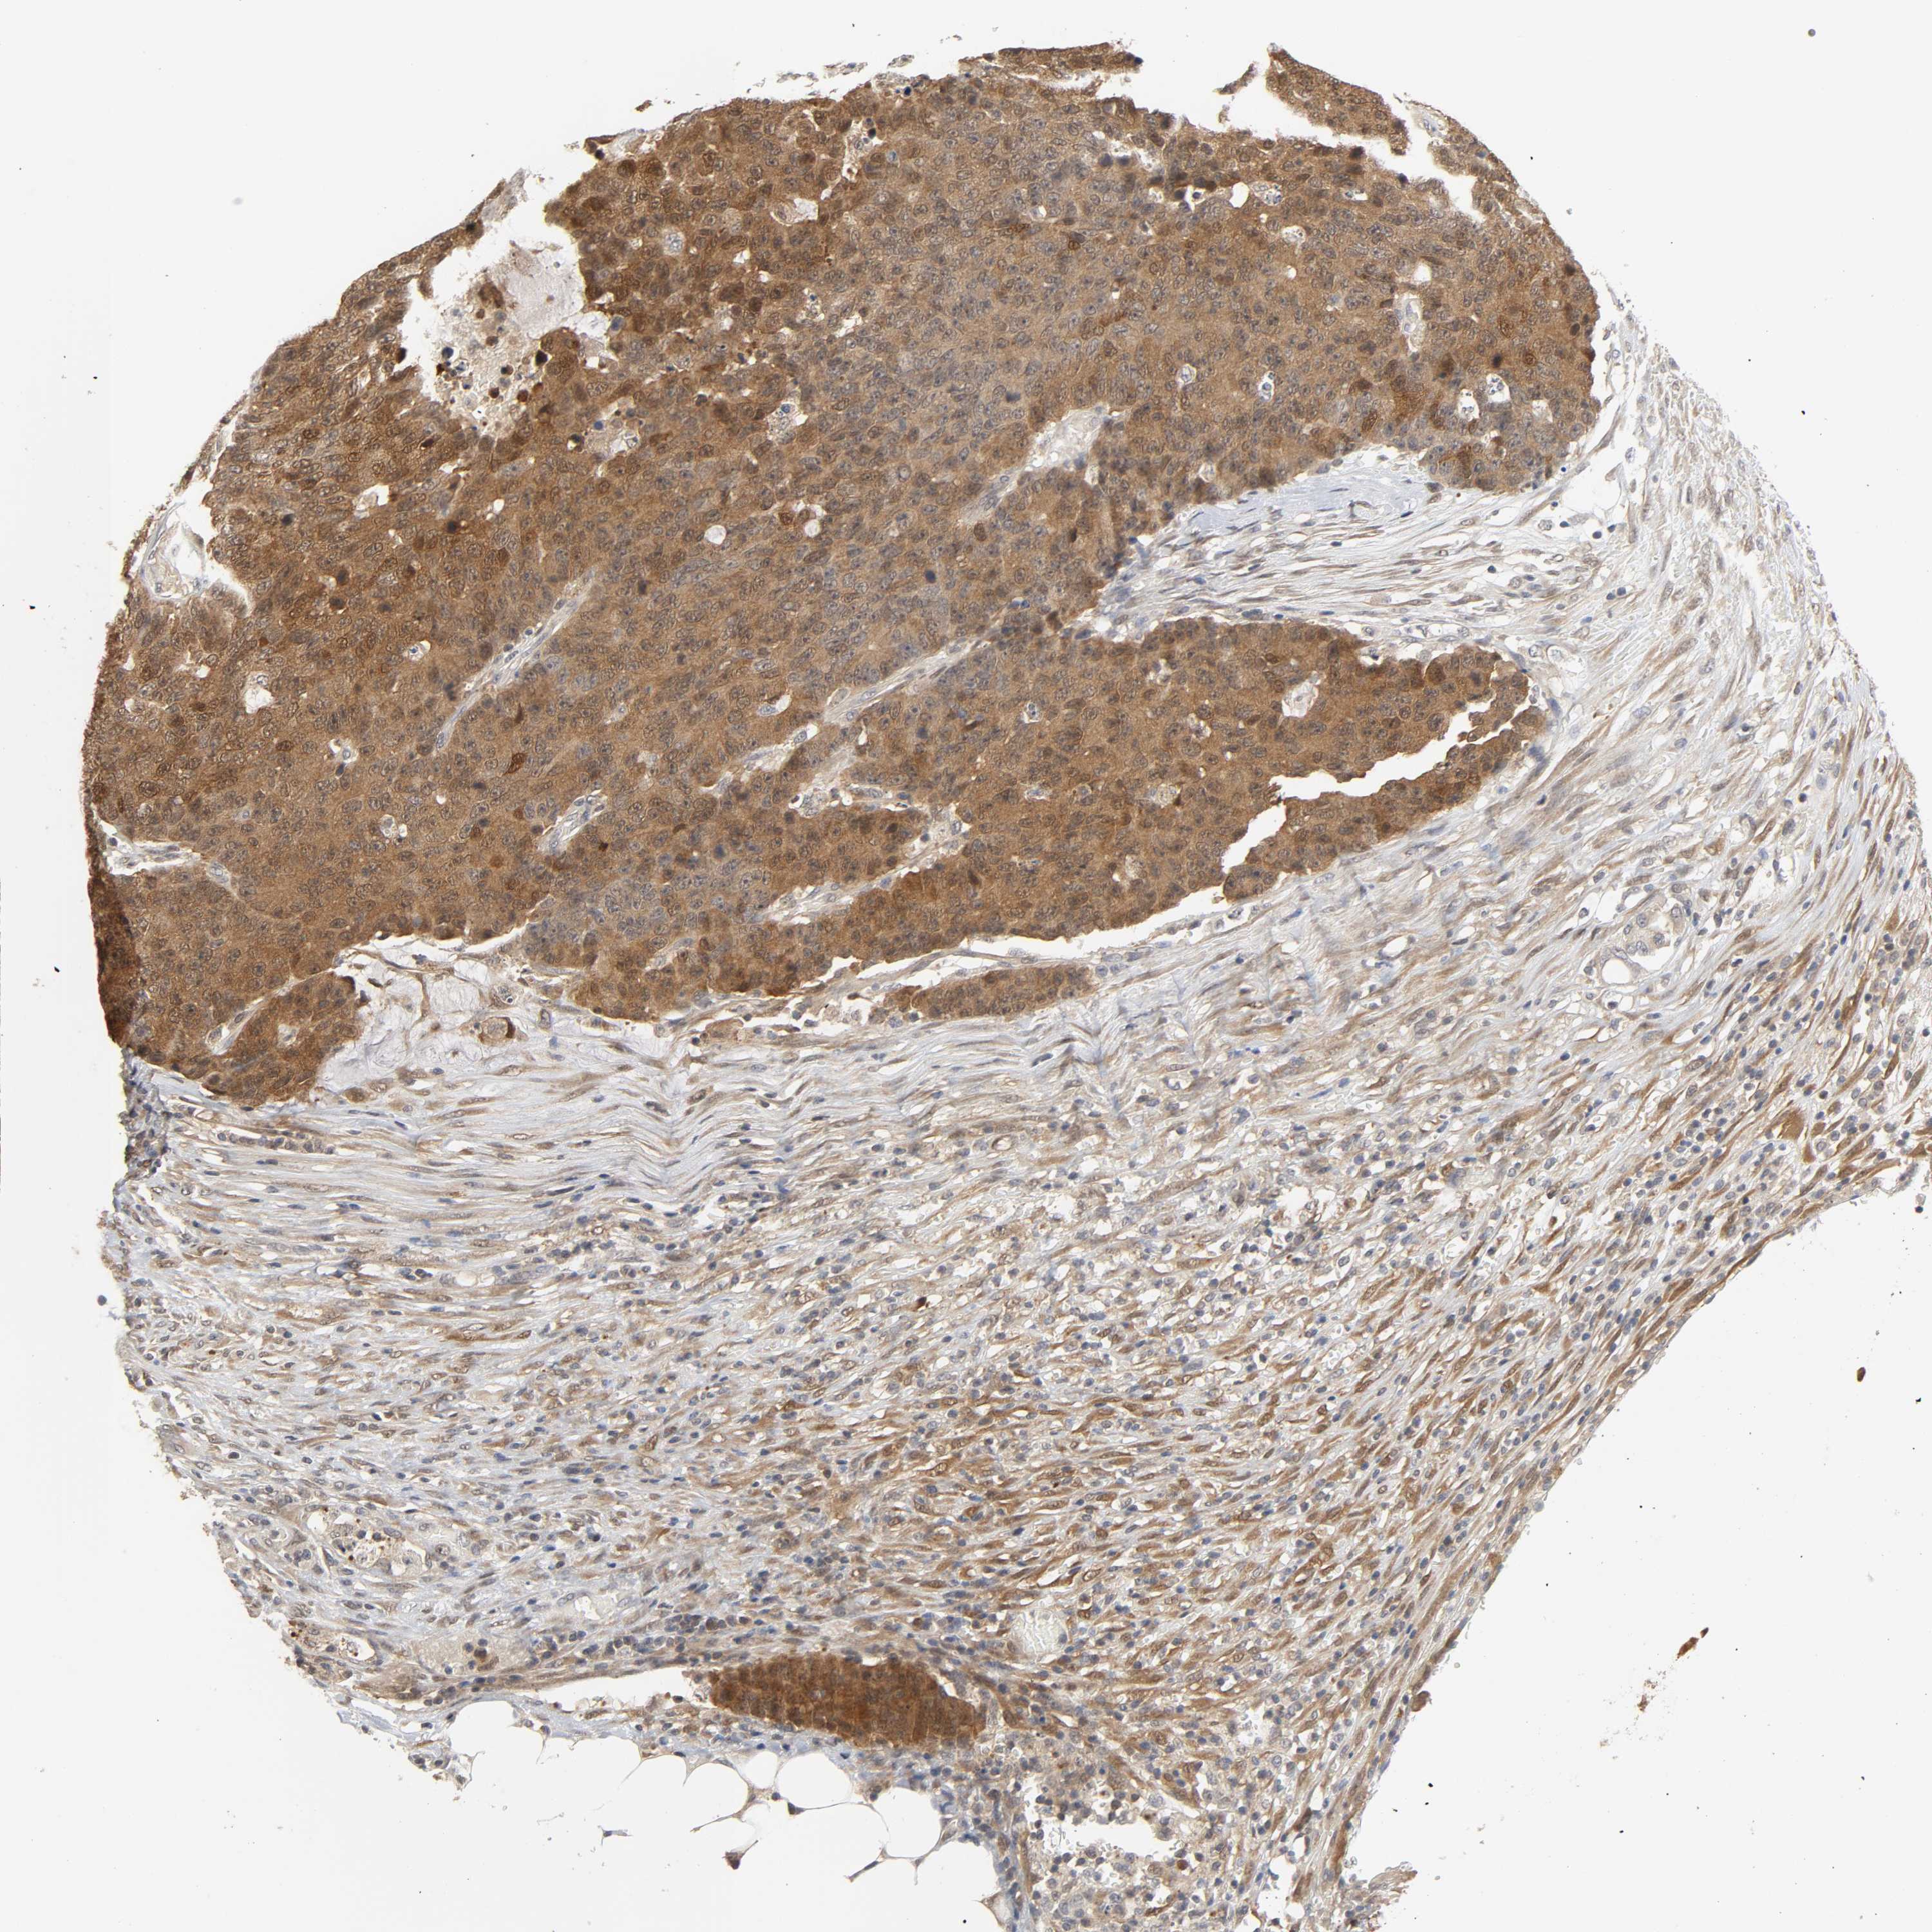

CANCER COLORECTAL CANCER Show tissue menu

Colorectal cancer

Human cancer

Colon adenocarcinoma

Rectum adenocarcinoma